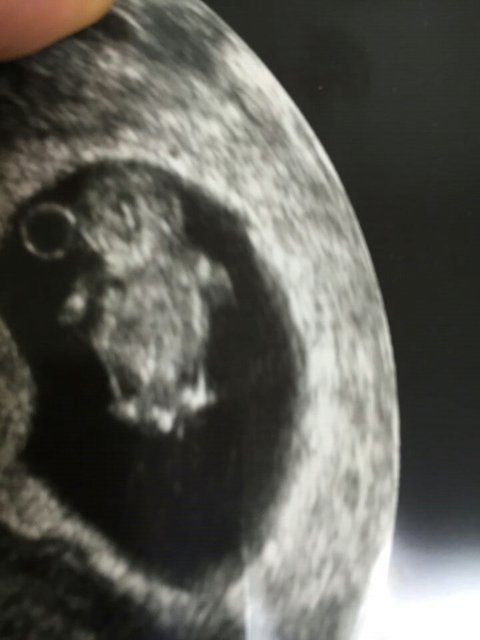

++)))))추가..

자작이라고 하는 분들 오해 풀어드릴까 해서 촘파 사진 같이올려요..

뭐 이것도 조작이다 못믿는다 하시는 분들까진 제가 어떻게 도와드릴 수가 없구요..

저는뱃속에 두달 조금넘은 애기가 있구요 혼전임신이라